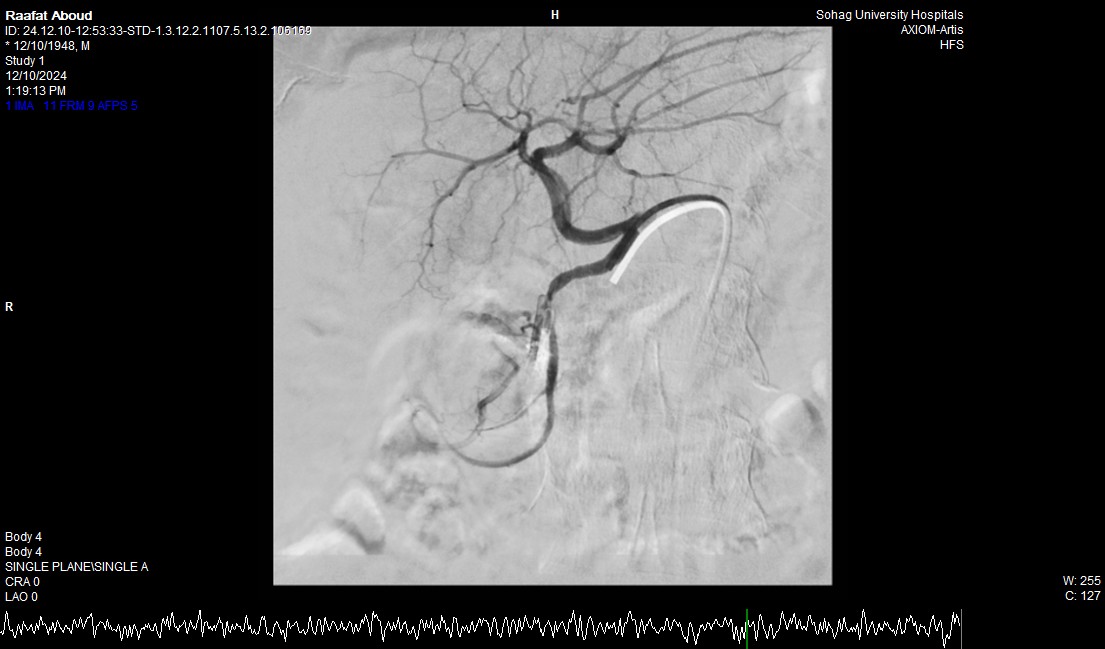

وأضاف الدكتور أحمد كمال المدير التنفيذي للمستشفيات الجامعية جامعة سوهاج، أنه بعد إجراء الفحوصات للمريض تبين وجود قرحة كبيرة بالإثنى عشر وشريان نازف، حيث نجح الفريق في التحكم المبدئي بالنزيف عن طريق تركيب مشبك معدني بالمنظار وحقن للقرحة النازفة، ثم تم استدعاء فريق أطباء وحدة الأشعة التداخلية على الفور وتم عمل غلق للشريان النازف بشكل عاجل من خلال جهاز القسطرة.

وأوضح الدكتور محمد زاكي رئيس قسم الأشعة، أن مثل هذه الحالات تعد من الطوارئ الطبية الخطيرة والتي تستوجب عمل قسطرة شريانية عاجلة لغلق الشرايين النازفه، مشيرًا أن وحدة الأشعة التداخلية تم تزويدها بجهاز أشعة محوري متقدم لاجراء مثل هذه الحالات، وأن هذا النجاح هو نتيجة لتعاون أقسام المستشفى مع وحدة الأشعة التداخلية لتقديم خدمة مميزة للمرضى.